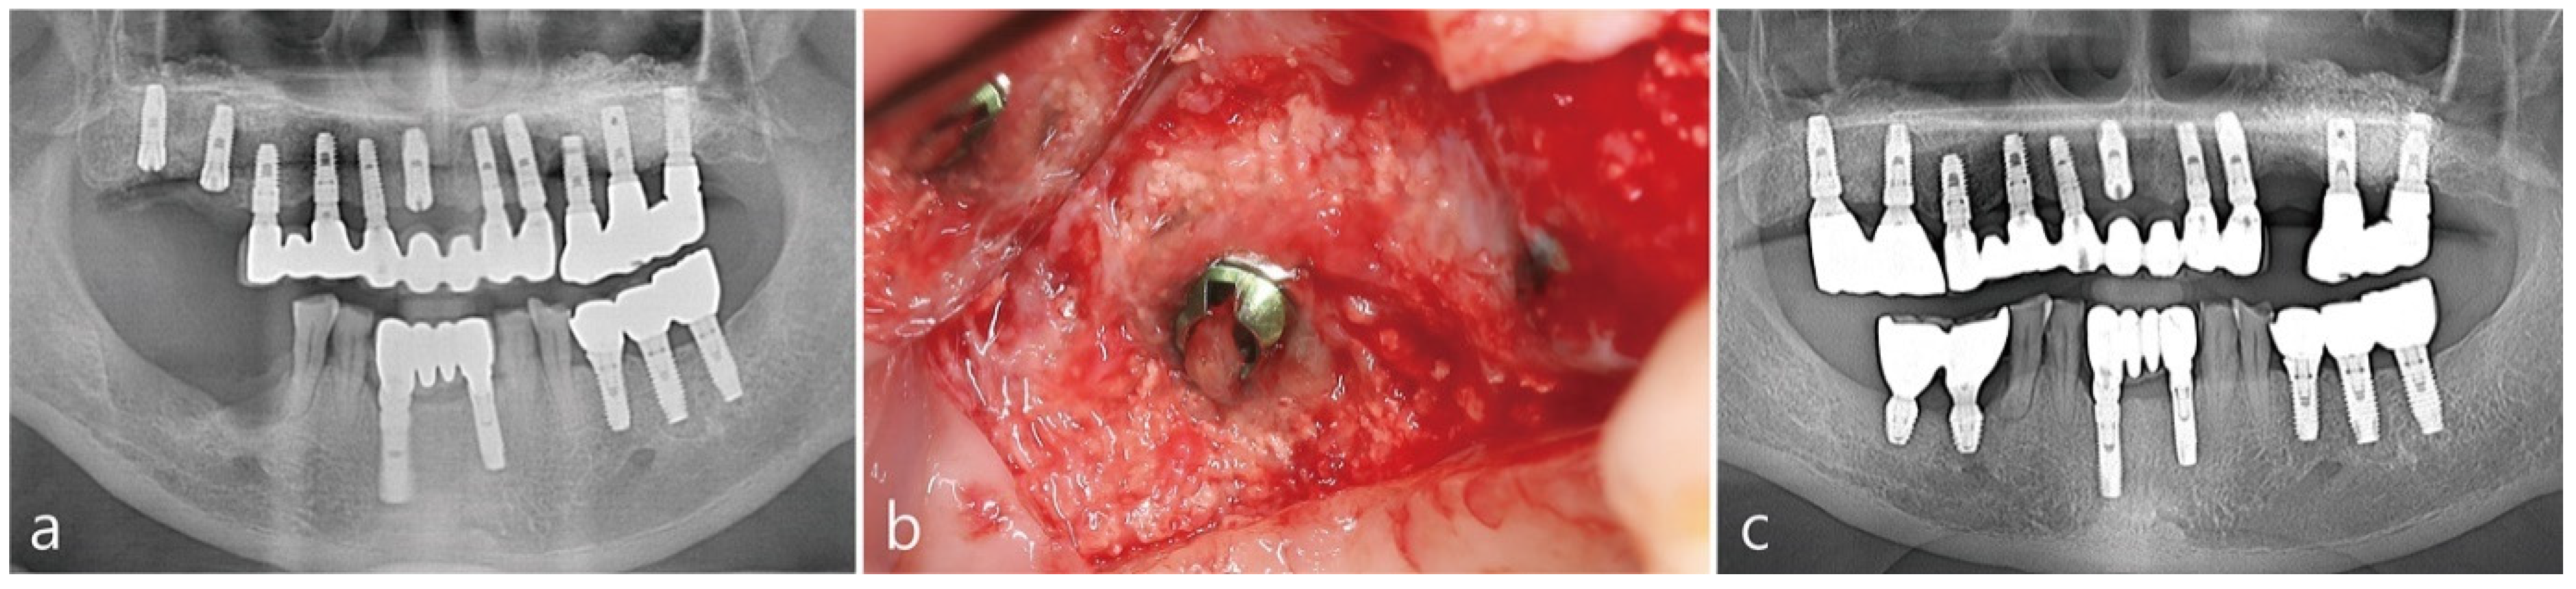

The patient is a 63-year-old non-smoking male suffering from severe chronic periodontitis. The patient underwent a bilateral maxillary sinus augmentation using DBBM (Bio-Oss®, Geistlich, Biomaterials, Wolhuson, Switzerland) 16 years ago. Implants were placed in the posterior maxillary region at the time of the sinus augmentation as shown in the pre-operative panoramic radiograph in Figure 1a. The lateral window site was covered with Gore-tex membrane (W.L Gore & Associates, Flagstaff, AZ, USA). 6 months after the surgery, the implants were uncovered and the Gore-tex membrane was removed. Two months after the second stage procedure, the final prosthesis was delivered. The patient was initially compliant for maintenance twice a year but eventually discontinued treatment at the clinic. After 16 years, the patient returned to the clinic due to hypermobility of the periodontally-involved maxillary right 1st molar. The maxillary right 1st molar was extracted and planned to be restored with an implant. 2 months post extraction, sufficient amount of bone was present in the previously augmented maxillary sinus as depicted in Figure 1b. However, ridge deficiency was observed in the edentulous ridge. In Figure 1c, the maxillary left 1st premolar implant and three mandibular right molar implants were also removed due to peri-implantitis.

Figure 1. (a) Pre-operative panoramic radiograph (b) Panoramic radiograph taken after the extraction of the maxillary right first molar (c) Panoramic radiograph taken after the extraction of the maxillary right second molar and removal of right posterior implants.